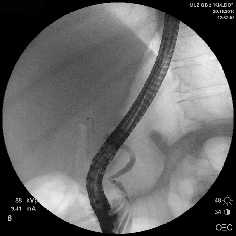

Рубцовая стриктура средней трети холедоха, холедохолитиаз

Полный блок средней трети холедоха (клипса на холедохе)

Несостоятельность культи пузырного протока

Рис. 1. Рентген-фото выявленной патологии

Rg-фото. Бужирование стриктуры холедоха

Rg-фото. Баллонная дилятация стриктуры холедоха

Rg-фото. Стентирование холедоха

Рис. 2. Наиболее часто выполняемые эндоскопические вмешательства